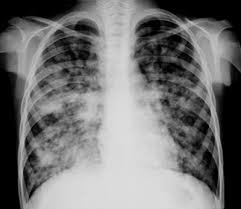

Este curso se desarrollará en formato de taller, que entregará herramientas a los profesionales que se desempeñan en el área respiratoria para interpretar de manera adecuada la imagenología de tórax.

- Anatomía para radiología

- Signos radiológicos

- Patrones radiológicos

- Evaluación de radiología de tórax

- Taller de interpretación.